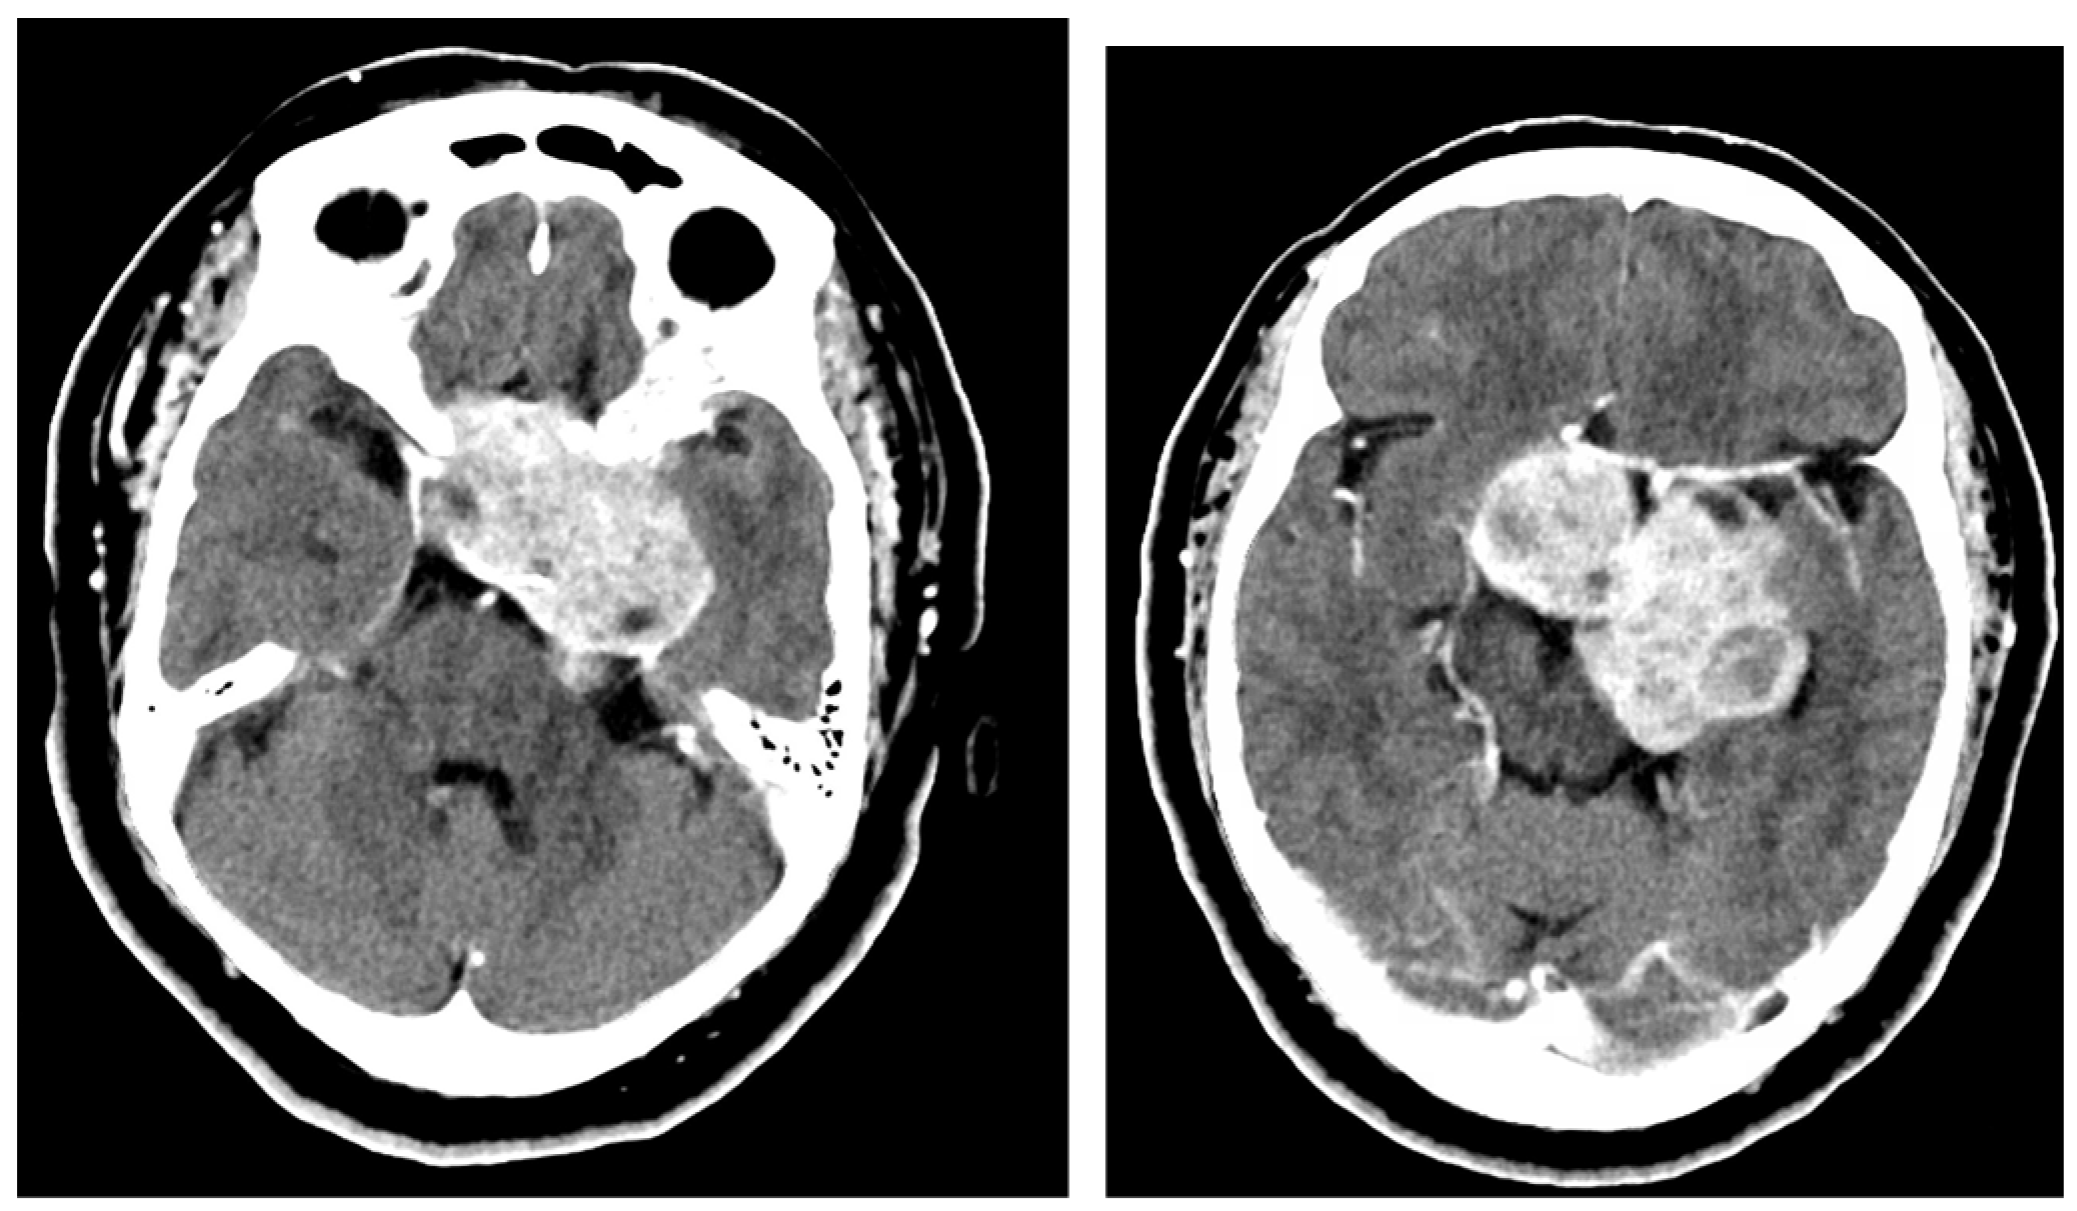

2.1. Case 1

2.2. Case 2